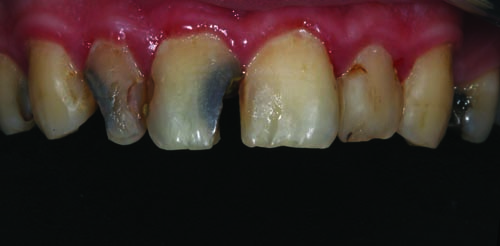

Fig. 5: Close-up retracted view of the maxillary central and lateral incisors. Examination revealed that teeth #7 and #8 presented carious lesions and periapical periodontitis (PAP) that would require root canal therapy. Tooth #10 had previously undergone root canal therapy, but no post or core had been placed.